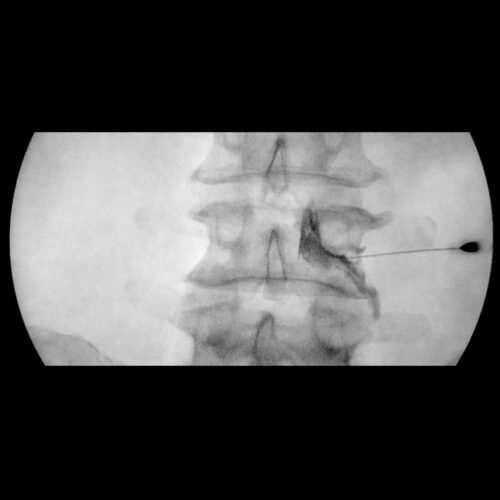

L’importanza dello Scottie Dog Sign nella Fluoroscopia del rachide in Terapia del Dolore

Nella gestione del dolore cronico, l’accuratezza nella diagnosi e nel trattamento è fondamentale. Un’immagine chiave che utilizziamo nella fluoroscopia del rachide è il famoso “Scottie…